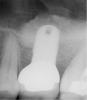

The 2-mm twist drill is used to create an osteotomy 1 mm short of the subantral floor. If any resistance is detected prior to reaching the 3-mm depth, drill penetration must be stopped, because the subantral cortical bone has possibly been reached. Any uncontrolled "push" would penetrate the bone and likely perforate the sinus membrane. A guide pin is then inserted and a radiograph taken to determine if drill penetration has terminated within 1 mm of the subantral floor (Figure 2). If the radiograph indicates that more than 1 mm of bone is present subantrally, the twist drill is used again to penetrate within 1 mm of the sinus floor. Alternately, an osteotomy tip for a piezosurgery unit can be used for this purpose. The final depth of penetration should be verified with another periapical film.

Figure 2  After drilling to a depth of 3 mm with a 2.1-mm twist drill, the guide pin was placed and a radiograph was taken to ascertain if the drill stopped within 1 mm of the subantral floor.

Figure 2